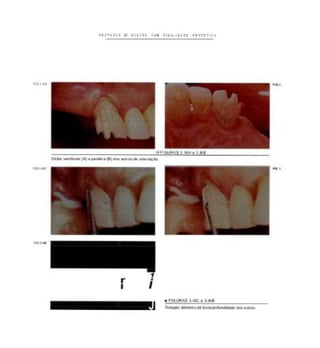

PIO J IA

• f IGURAS 3 IAE ) IB

lA)Vista vestferiar dlmca e(B) no modelo doa o****» preparados. Aores.

para aumenta» a f»t«oçfto da prótese.

n a J C

a FIGURAS 3.IBa 3.1 D

(C)Vtsiasocluaaldomodetode uaoa no a (D), do caso concluído.